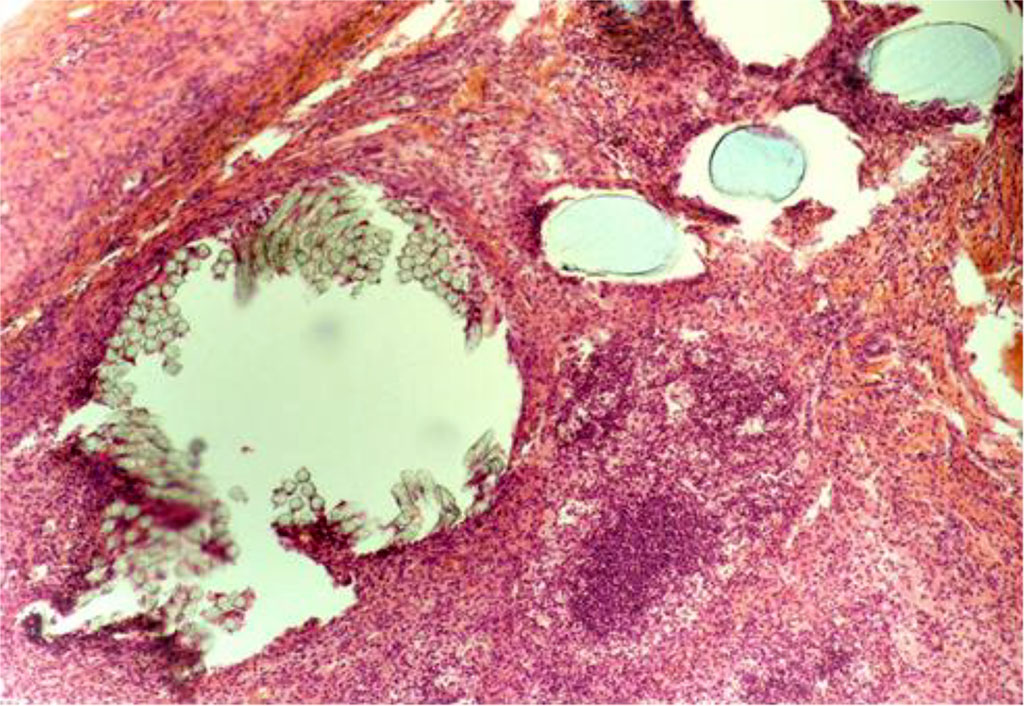

By Day 14 of the experiment, the animals of the CG were diagnosed with a decrease in the population of leukocytes and an increase in the number of histiocytes and lymphocytes. At the same time, sporadic siderophages were visualized, as well as giant cells of phagocytosis (Figure 3). The thickness of IC in the circumference of the PP-MI fragments was 46.724±0.310 μm.

Fig. 3. AAW of the CG animal by Day 14 of the experiment. Staining with H&E. ×10